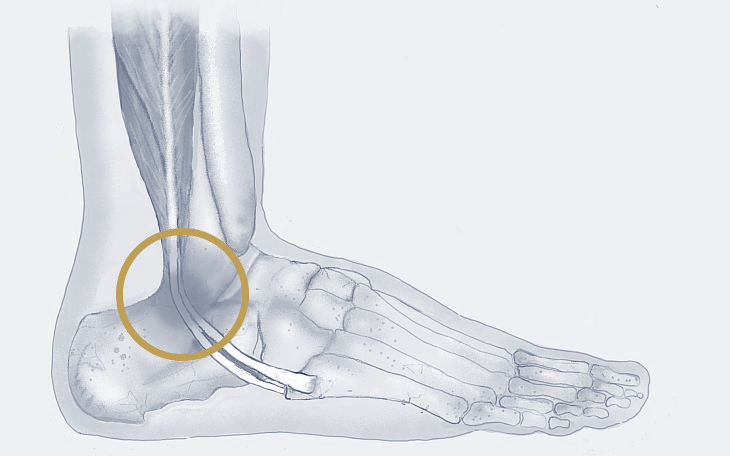

Bildquelle: www.docset.de

Symptome

Typisch sind Schmerzen an der Außenseite des Knöchels, die sich bei Belastung verstärken. Je nach Art der Pathologie können auch Schwellung, Instabilität des Sprunggelenks oder ein Knacksen beim Bewegen des Fußes auftreten.

Ursachen

Häufige Ursachen sind Überlastung, Verletzungen (z. B. Umknicken), Fußfehlstellungen oder auch falsches Schuhwerk.

Konservative Therapie

Entlastung, Kühlung, entzündungshemmende Medikamente, Ruhigstellung in einer Schiene oder Orthese, Physiotherapie zur Kräftigung der Muskulatur und Verbesserung der Koordination können die Beschwerden lindern. Auch eine Stoßwellentherapie kann hier Linderung verschaffen.

Operative Therapie

Wenn die konservativen Maßnahmen nicht ausreichend helfen, kann eine Operation in Erwägung gezogen werden. Dabei werden je nach Art der Pathologie verschiedene operative Verfahren eingesetzt, wie z. B. die Naht oder Rekonstruktion der Sehne, die Stabilisierung der Sehnen in ihrer Rinne oder die Korrektur von Fußfehlstellungen.